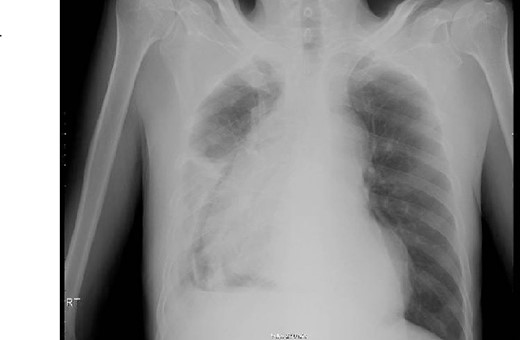

This is a 65-year-old male who was diagnosed with poorly differentiated adenocarcinoma of the esophagus in an outside hospital 4 months prior to his presentation. Endoscopy done previously showed lower esophageal fungating mass that was partially obstructing the lumen. Biopsies taken showed adenocarcinoma. Patient staging work up was negative for metastasis. He received neo-adjuvant chemotherapy and underwent esophagectomy with gastric pull-up 6 weeks before his presentation. He presented to our hospital with a history of progressive shortness of breath, fever, fatigue, loss of appetite, cough, dysphagia, and voice hoarseness. Upon examination, there was a decreased air entry on the right side of the chest with right lung opacity seen on chest X-ray (Fig. 1). CT chest scan showed right posterior mediastinal heterogeneous mass, suggestive of hematoma with pleural thickening (Fig. 2). The patient was booked for right video-assisted thoracoscopic surgery. During the procedure, a right lesion occupying the whole right hemithorax was identified with multiple chest wall nodules, and all were biopsied. After the operation, the patient developed septic shock and eventually went into renal failure, respiratory failure, and cardiac arrest. Patient deceased 24 days after admission.